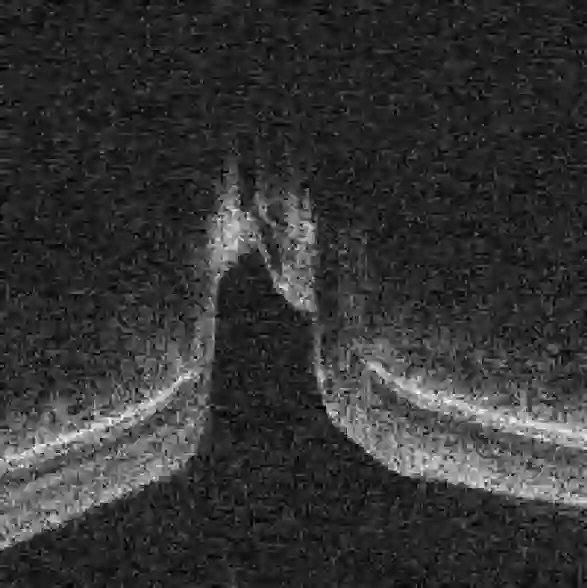

Fairness in artificial intelligence models has gained significantly more attention in recent years, especially in the area of medicine, as fairness in medical models is critical to people's well-being and lives. High-quality medical fairness datasets are needed to promote fairness learning research. Existing medical fairness datasets are all for classification tasks, and no fairness datasets are available for medical segmentation, while medical segmentation is an equally important clinical task as classifications, which can provide detailed spatial information on organ abnormalities ready to be assessed by clinicians. In this paper, we propose the first fairness dataset for medical segmentation named Harvard-FairSeg with 10,000 subject samples. In addition, we propose a fair error-bound scaling approach to reweight the loss function with the upper error-bound in each identity group, using the segment anything model (SAM). We anticipate that the segmentation performance equity can be improved by explicitly tackling the hard cases with high training errors in each identity group. To facilitate fair comparisons, we utilize a novel equity-scaled segmentation performance metric to compare segmentation metrics in the context of fairness, such as the equity-scaled Dice coefficient. Through comprehensive experiments, we demonstrate that our fair error-bound scaling approach either has superior or comparable fairness performance to the state-of-the-art fairness learning models. The dataset and code are publicly accessible via https://ophai.hms.harvard.edu/harvard-fairseg10k.